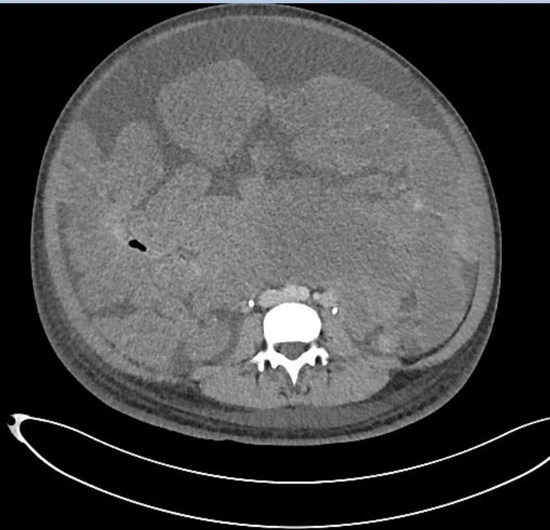

他把那里比作“布满鹅卵石的海滩”。原本应该是肠管的位置看不到一段肠子,只有挤作一团的肿瘤。腹腔内唯一可见的正常器官是胃的下部。血管被挤到一旁,由于供养着密密麻麻、黄豆到蚕豆大小的肿瘤,直径变成正常血管的3倍。

“无从下刀”,他用手摸,肿瘤的质地较软、呈粉红色,看上去、摸起来都与肠管无异。卵巢和子宫隐藏在盆腔深处。

前进的路上布满“雷区”。下腔静脉的管壁如纸一样薄,一旦破裂出血就是上千毫升。肠管管壁的厚度也只有1-2毫米,一旦损伤,重则引发致命性腹膜炎、感染性休克,轻则患者6个月内无法进食,只能从静脉输入营养物质。

肿瘤太多,一个一个切太慢,谭先杰决定使用“卷地毯式”,彻底清除肠管和膀胱表面成串的肿瘤,“就是从它们的表面扒掉一层,还不能扒太多。”

接着他用手术刀将将布满肿瘤的腹膜从其下的器官表面剥离出来,用手脱出,“兜满瘤子,像口袋一样”。

3小时后,“地毯”卷走,子宫和双侧卵巢终于显露出来,“柳暗花明又一村”。

切下的瘤子快要从4个口径22厘米、容积1000毫升的手术大盆和1个手术弯盘中溢出来。谭先杰把它们铺满100厘米×100厘米的手术大单上,花了10多分钟计数。

肿瘤一共1150多枚,手术中瘤体内带走的血液足有2600毫升,约5斤重。其中最大的瘤子尺寸18厘米×15厘米×8厘米,最小的只有黄豆大小。去掉几大块被送去病理检查的肿瘤,余下肿瘤重18斤。